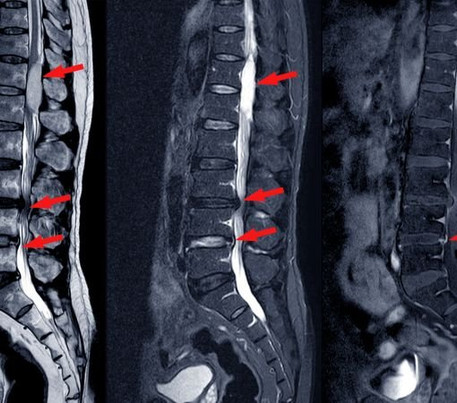

The physical environment at Synapse Spine reflects its subspecialty focus. Consultation rooms are designed to facilitate detailed discussions, often supported by imaging studies such as MRI and CT scans. During my visit, I observed clinicians reviewing scans alongside patients, explaining findings in accessible language.

Lumbar spine stenosis is a condition characterized by narrowing of the spinal canal in the lower back, leading to compression of nerves. Patients commonly report lower back pain, leg pain, numbness, tingling, or difficulty walking for extended periods.

At Synapse Spine, clinicians explained that stenosis often develops due to age-related degeneration, disc bulges, thickened ligaments, or arthritic changes. While symptoms may progress gradually, early evaluation plays a key role in preventing functional decline.